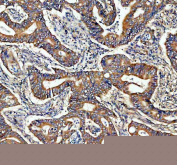

IHC staining of FFPE human lung adenocarcinoma tissue with ADAM10 antibody, HRP-secondary and DAB substrate. HIER: boil tissue sections in pH8 EDTA for 20 min and allow to cool before testing.